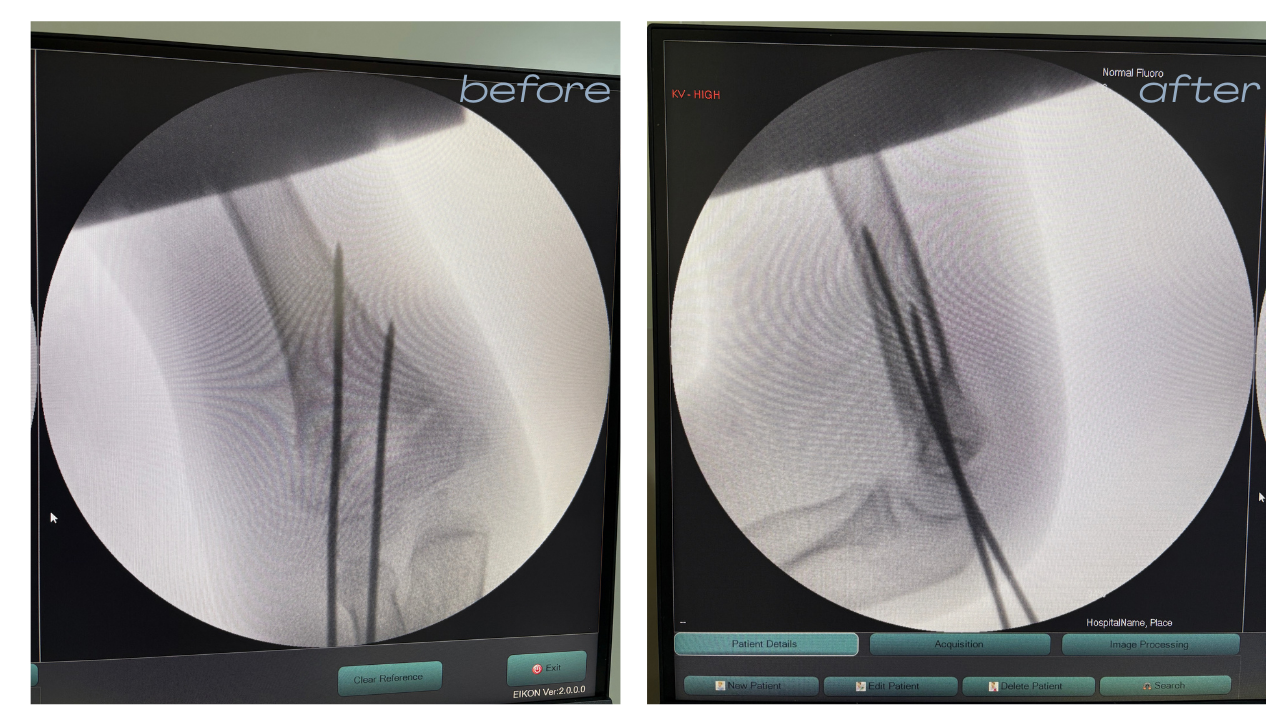

Accident & Trauma Care – Specialized in Bone & Joint Injuries.

- Trauma & Fracture:

Emergency Bone Care.

Known for a results-driven approach that prioritizes minimally invasive techniques and rapid post-surgical rehabilitation.